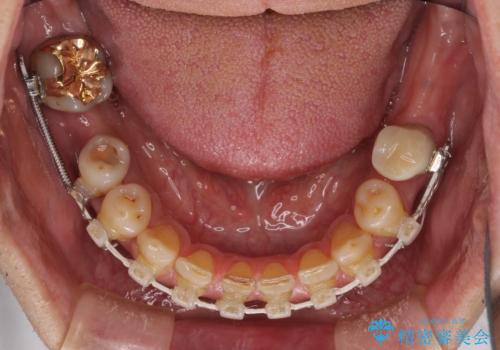

下顎の部分矯正を行ってから奥歯の補綴治療とインプラント治療

また、下顎前歯にはスペースがあり、コンポジットレジンでスペースを閉じている状態だったので、前歯のスペースを解消しつつ、奥歯にスペースを獲得するよう矯正治療を行うこととしました。

奥歯1歯分を動かすには時間がかかるため、矯正治療には思いの外時間がかかりました。

痛みのある奥歯は必要に応じて根管治療を行い、左下インプラントは角化歯肉の移植により清掃性を向上させ、気になっていた部分をしっかりと改善させることができました。